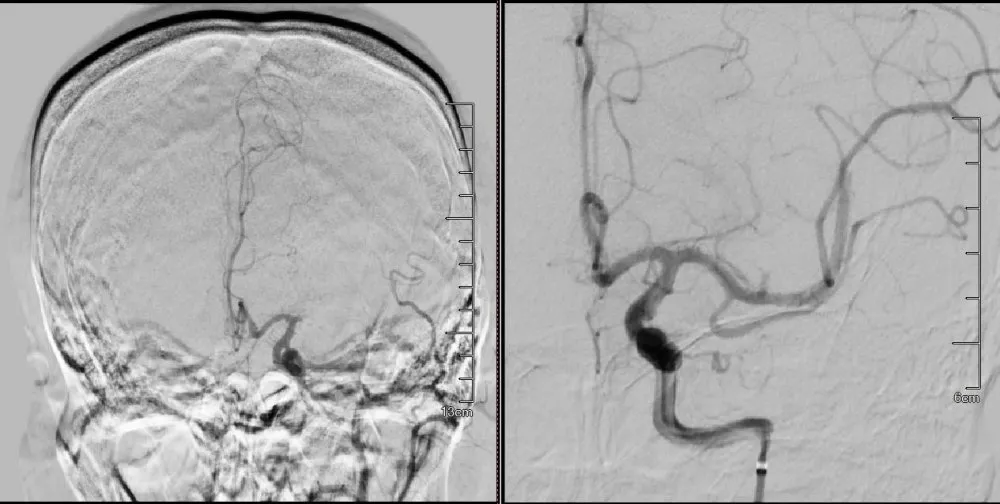

为抢救病人,将其第一时间收入ICU密切监护,同时再次发起神经内科、神经外科、呼吸科、ICU多学科会诊,评估后紧急溶栓治疗,1小时后,患者意识转清,缺氧明显改善,生命体征稳定。说明肺栓塞溶栓成功,但患者肢体肌力恢复欠佳。神经外科会同神经内科慎重讨论后,为患者行脑血管造影,术中见左侧大脑中动脉近端闭塞,再次与家属沟通后,在全麻下行左侧大脑中动脉M1段取栓术,手术过程顺利,一次取栓成功。

脑血管介入取栓前后影像